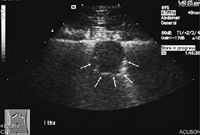

Although the most accurate way to definitively diagnose a pulmonary mass is through surgery and histologic examination, other less-invasive diagnostic techniques, such as cytology, may be attempted first. Fine-needle aspiration appears to be the safest and most convenient method of harvesting cytologic samples for initial diagnosis (Figure 3). A recent study comparing cytologic and histologic diagnosis of pulmonary neoplasia revealed that cytologic samples retrieved with 25- to 27-ga needles showed agreement with histologic diagnosis in 82% of cases, with 100% specificity and 77% sensitivity.30 As would be expected, cytologic accuracy for diagnosing neoplasia is higher with ultrasound guidance vs. blind aspiration, as visualization of the suspect primary lung tumors is necessary to maximize appropriate sample collection (Figure 4).30 Fluoroscopy also facilitates the accurate and efficient retrieval of cellular samples from suspect pulmonary tumors.31

4. A thoracic ultrasonogram in a dog with a peripherally located primary lung tumor demonstrates a hypoechoic lesion immediately adjacent to the thoracic wall (arrows). Ultrasound-guided fine-needle aspiration improves the chances of a diagnostic sample. (Photograph courtesy of Dr. Laura Garrett.)